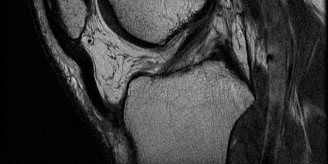

Given the patient's refractory symptoms at the three-month mark and the new onset of localized medial catching, advanced imaging via Magnetic Resonance Imaging (MRI) is indicated to evaluate the soft tissue structures and articular cartilage. MRI provides unparalleled visualization of the chondral surfaces, the medial patellofemoral ligament (MPFL), and the synovial plicae.

The axial T2-weighted fat-suppressed images reveal a thickened, fibrotic medial synovial plica extending from the medial capsule and impinging upon the medial femoral condyle during flexion. There is associated focal bone marrow edema in the medial patellar facet and the opposing medial femoral condyle, representing early chondromalacia patellae (Grade II chondral fissuring). The MPFL is intact with no signs of acute or chronic tearing. The tibial tubercle-trochlear groove (TT-TG) distance is measured at 14 mm, which is within the normal limits (<15 mm is normal, 15-20 mm is borderline, >20 mm is abnormal), suggesting that her maltracking is driven by soft tissue imbalance and dynamic kinetic chain deficits rather than static bony malalignment.

The initial diagnostic sweep confirms a normal anterior cruciate ligament, intact menisci, and normal articular cartilage in the tibiofemoral compartments. Attention is then turned to the patellofemoral compartment. A thick, fibrotic Type C medial synovial plica is identified extending from the medial capsule and impinging heavily on the medial femoral condyle during dynamic flexion of the knee from 30 to 70 degrees.